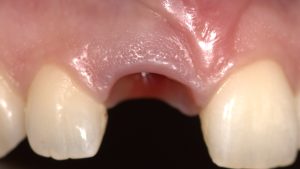

Level 1 Case: Socket shield technique

initial state Surgical stage after initial healing Final Restoration The future of the aesthetic zone…